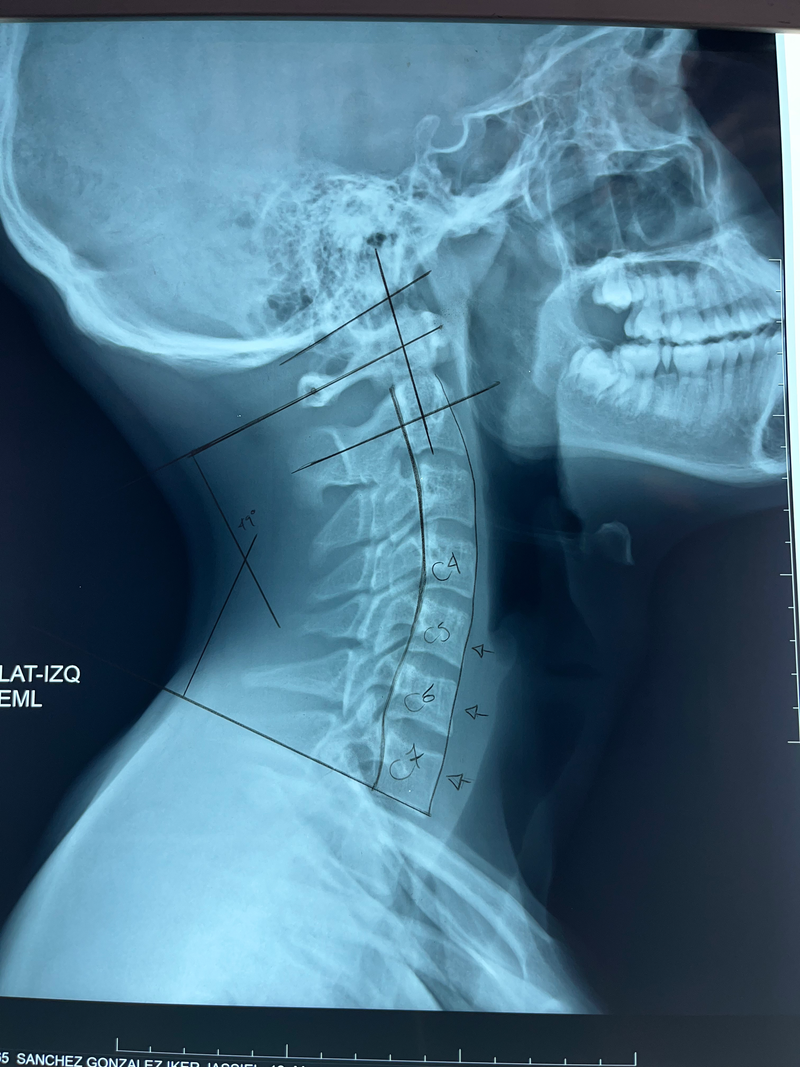

Analizar tu columna es muy importante para identificar la causa de tu dolor y prevenir cambios degenerativos o estructurales que puedan afectar tu calidad de vida y adecuado funcionamiento de tu cuerpo.

utilizamos los estudios competentes para brindar un diagnóstico preciso sobre las condiciones de tu columna.

Realizamos valoración con técnicas de análisis como Motion Palpation, valoración muscular para brindar un ajuste especifico y certero en tu columna.